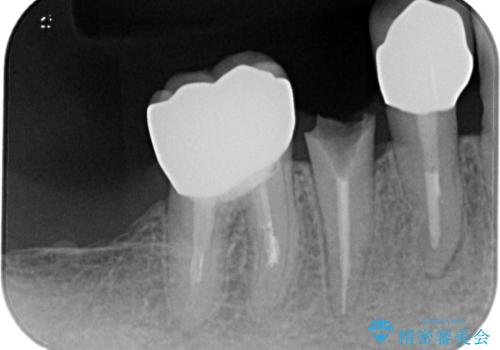

- 奥歯に装着していたクラウンが外れてしまったとのことで来院された患者様です。

診察したところ、歯根に破折線が確認され抜歯が必要な状態でした。

歯肉や歯槽骨の状態は良好であったため、抜歯即時埋入インプラントによる補綴治療を行うこととしました。

抜歯、インプラント埋入、仮歯の装着を1度に行うことができ、治療終了までわずか3か月で終えることができました。